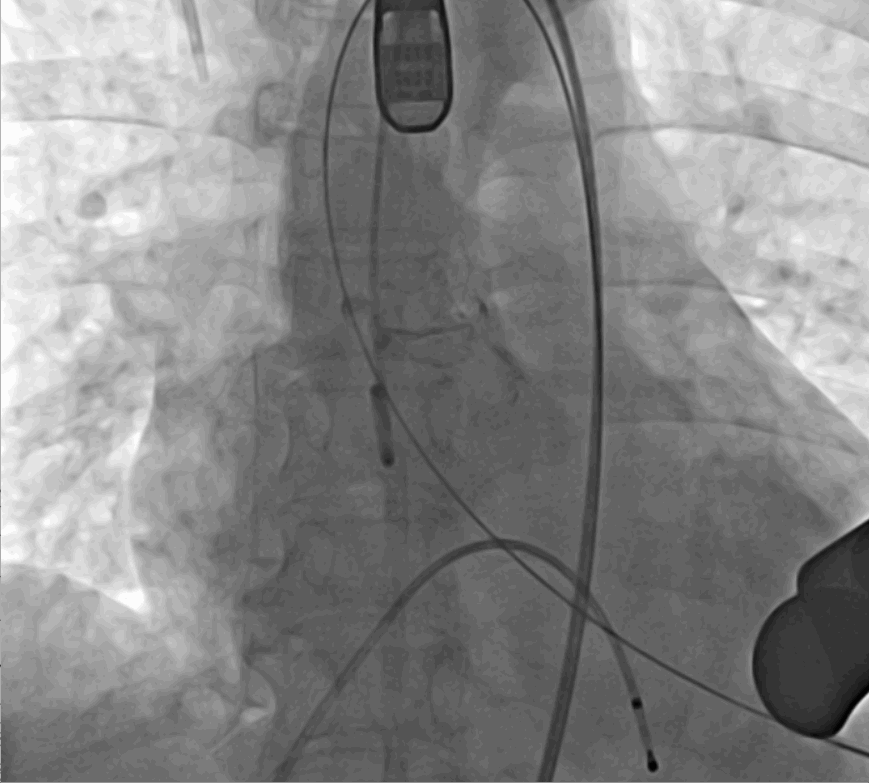

術(shù)后DSA影像

手術(shù)采用經(jīng)心尖入路,對患者進(jìn)行全麻后,在左側(cè)心尖處做3-4cm微創(chuàng)手術(shù)切口,在DSA及超聲引導(dǎo)下手術(shù)順利完成。從導(dǎo)入器械到完成瓣膜置入,僅耗時約10分鐘。術(shù)后即刻主動脈瓣返流程度由術(shù)前大量返流轉(zhuǎn)為消失,患者于導(dǎo)管室拔除氣管插管,次日由ICU轉(zhuǎn)入普通病房。